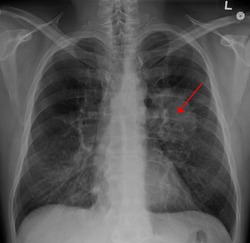

| A chest X-ray showing a tumor in the lung (marked by arrow) | |

Performing a chest radiograph is one of the first investigative steps if a person reports symptoms that may suggest lung cancer. This may reveal an obvious mass, widening of the mediastinum (suggestive of spread to lymph nodes there), atelectasis (collapse), consolidation (pneumonia) or pleural effusion.[1] CT imaging is typically used to provide more information about the type and extent of disease. Bronchoscopy or CT-guided biopsy is often used to sample the tumor for histopathology.[13]

Lung cancer often appears as a solitary pulmonary nodule on a chest radiograph. However, the differential diagnosis is wide. Many other diseases can also give this appearance, including metastatic cancer, hamartomas, and infectious granulomas such as tuberculosis, histoplasmosis and coccidioidomycosis.[61] Lung cancer can also be an incidental finding, as a solitary pulmonary nodule on a chest radiograph or CT scan done for an unrelated reason.[62] The definitive diagnosis of lung cancer is based on histological examination of the suspicious tissue[6] in the context of the clinical and radiological features.[12]